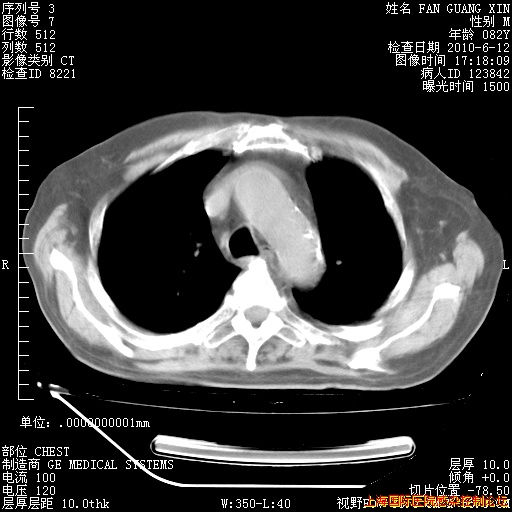

6月12日纵膈窗